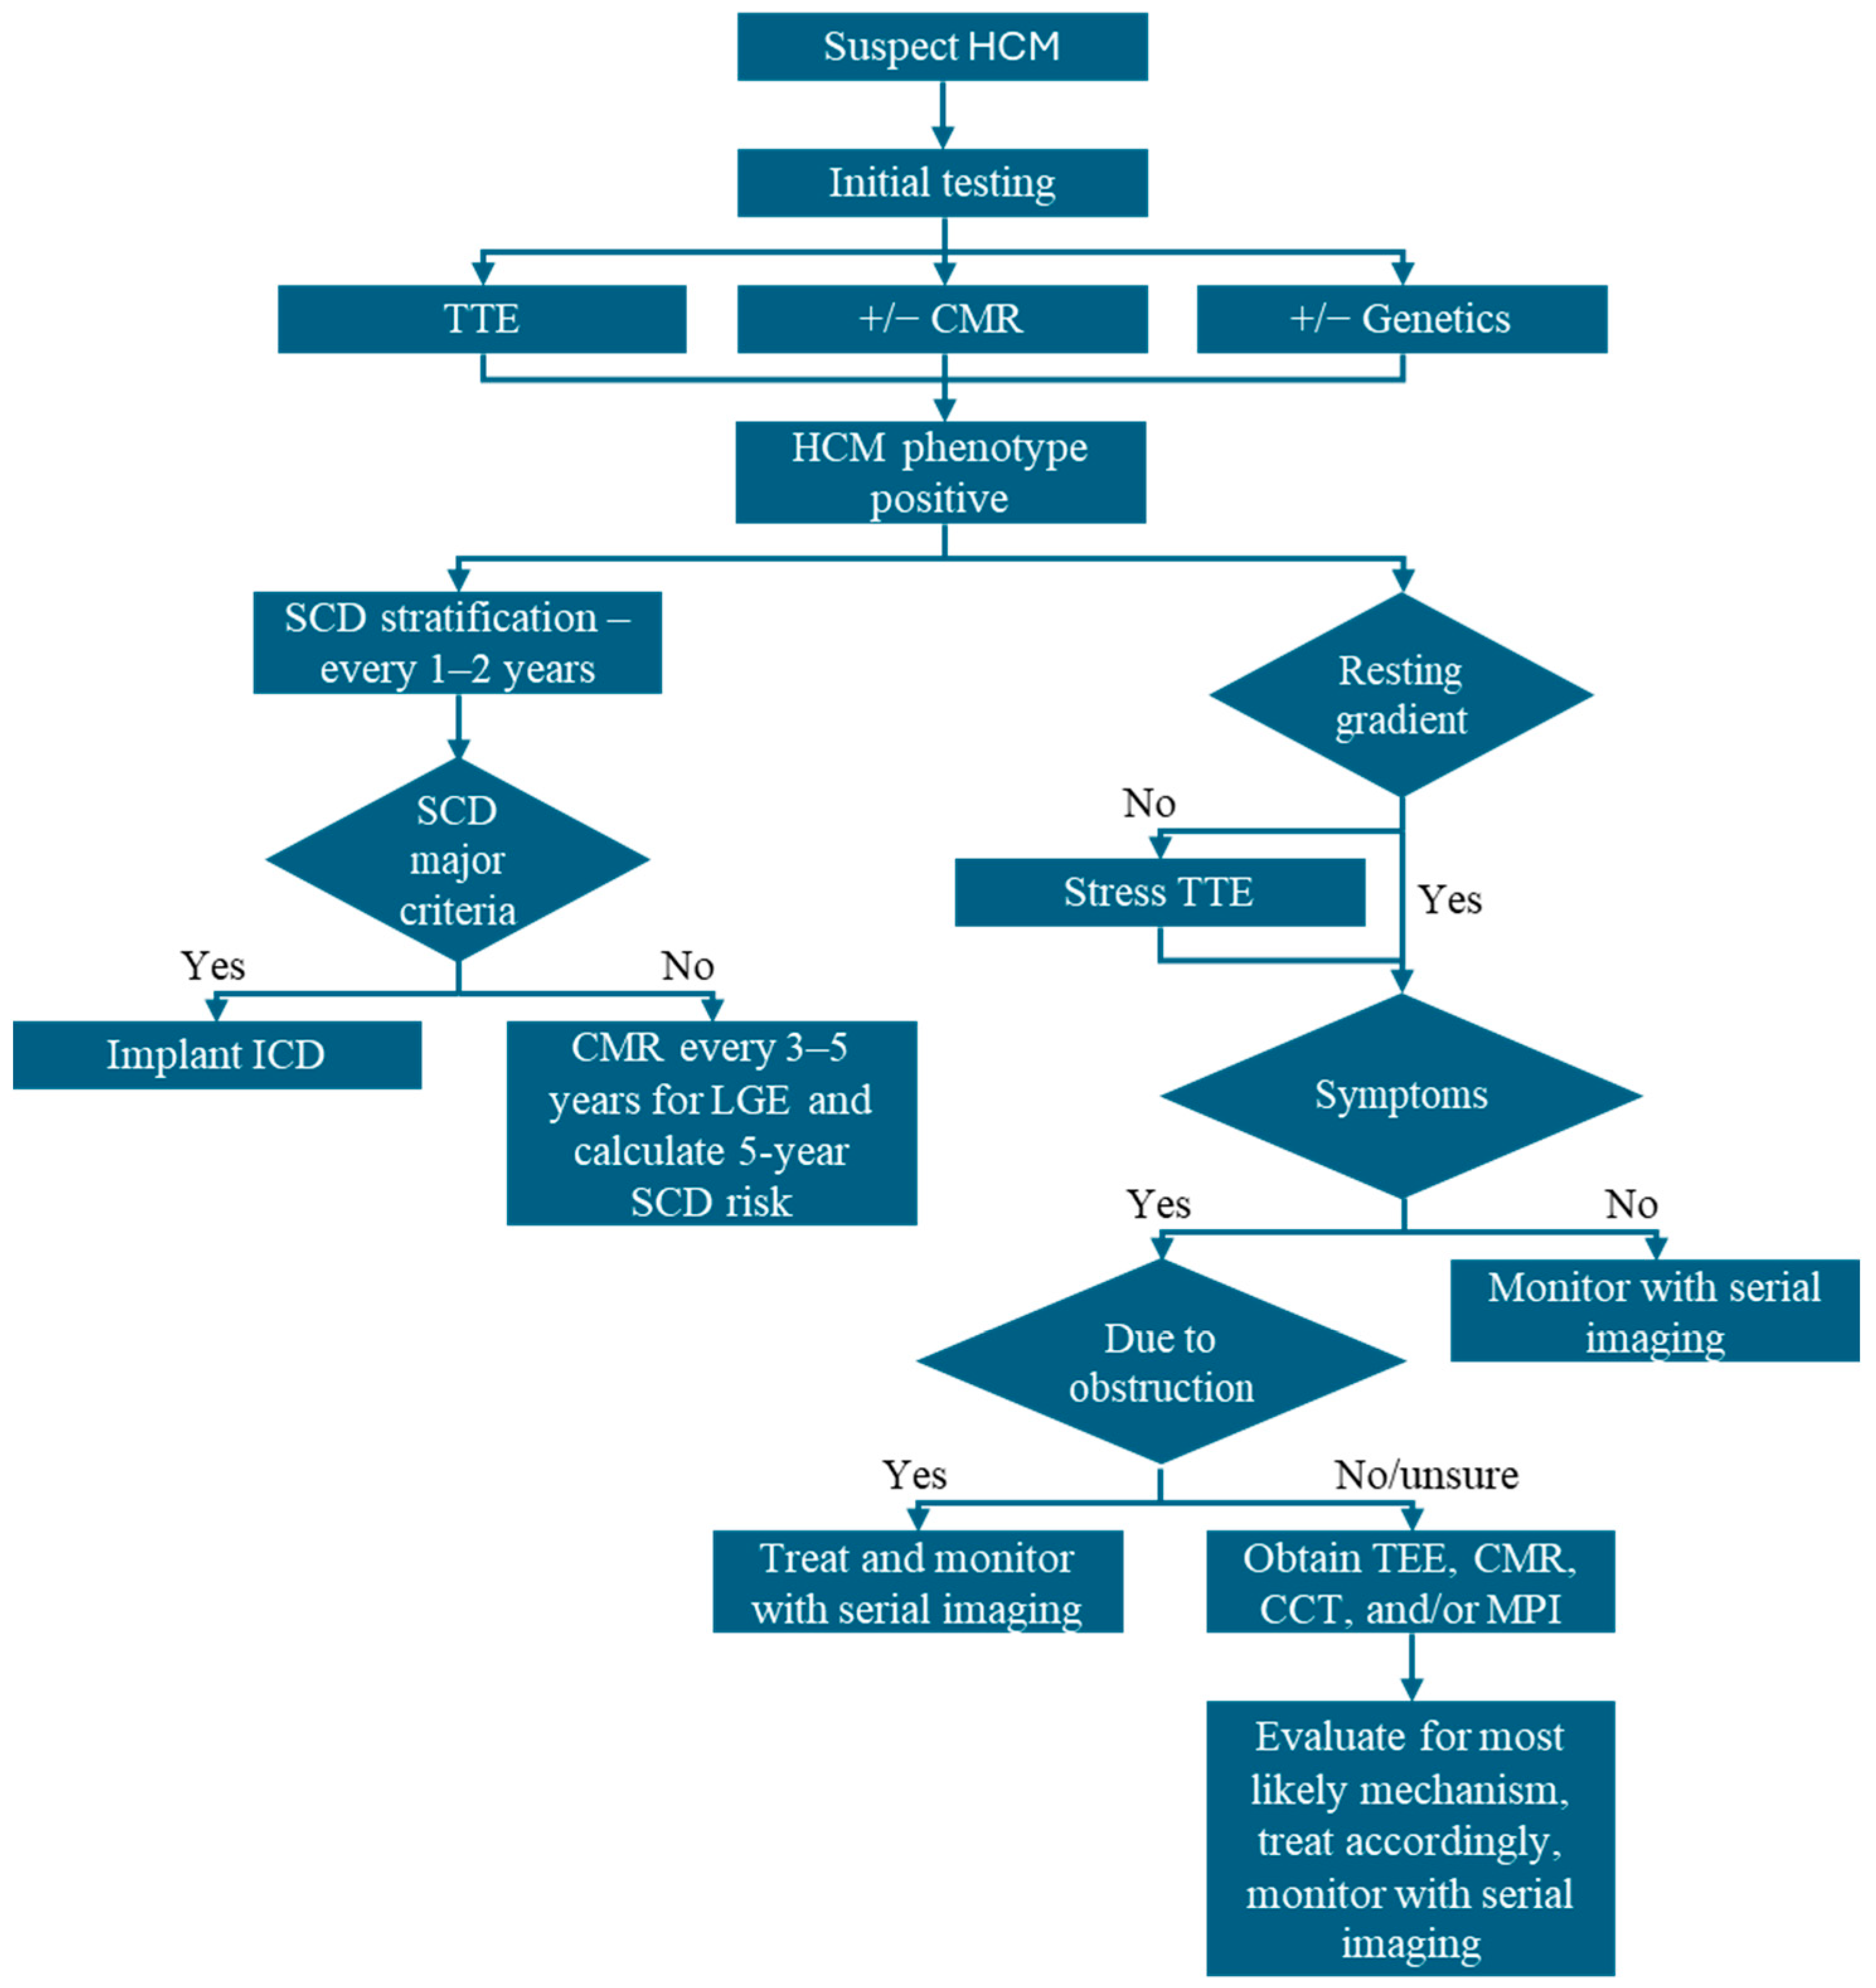

4. Imaging-Guided Management of HCM

4.1. Diagnosis and Classification

4.2. Symptom Management and Treatment of LVOTO

4.3. Risk Stratification for SCD and ICD Implantation

4.4. Assess Response to Therapy and Reverse Remodeling

5. Conclusions